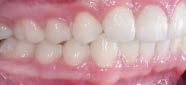

Estudios intraorales finales

Se observa el cierre de la mordida, la línea media inferior desviada 1 mm hacia la derecha respecto a la línea

media superior, el overjet de 2 mm y un overbite del 20%, (Figura 6).

Se obtuvo clase I molar bilateral y clase I canina bilateral (Figura 7).

En las fotografías oclusales observamos la forma de arco oval, la solución del apiñamiento y el cierre de la mordida abierta. (Figura 8)